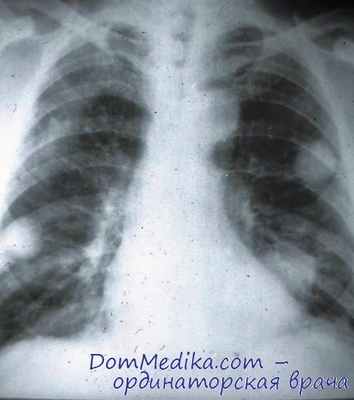

• Рентгенологические признаки — диффузные легочные инфильтраты и симптом «матового стекла» при МСКТ.